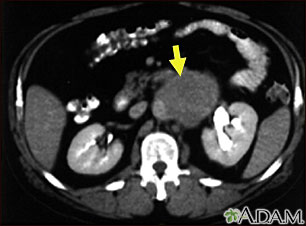

A CT scan of the middle abdomen showing a large tumor mass due to metastasis (spreading cancer) in abdominal lymph nodes.